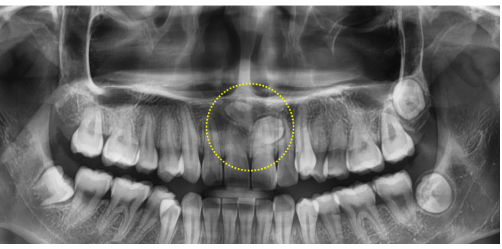

20대 여성 환자의 파노라마 엑스레이에서 매복 과잉치 2개가 발견되었습니다.

→ 교정 전 과잉치를 제거해 치아이동을 원활하게 할 수 있었습니다.